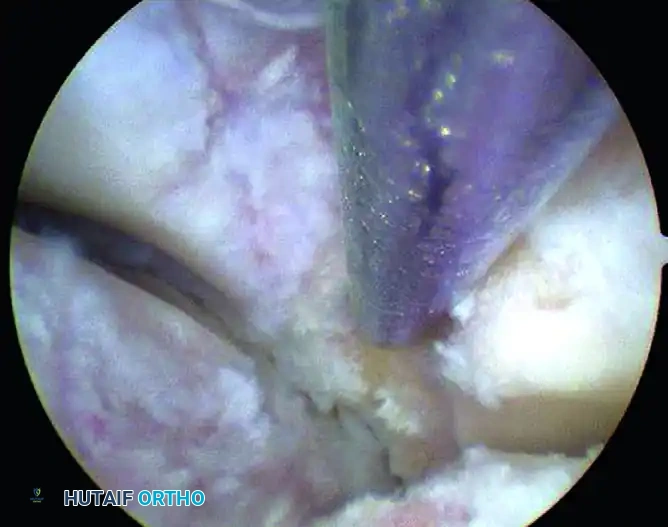

Image

FIGURE 50-16 A, Arthroscopic visualization of a focal osteochondral lesion on the first metatarsophalangeal joint.

For the treatment of osteochondral lesions, the following steps are executed:

1. Debridement: The unstable cartilage flaps surrounding the lesion are excised using a small arthroscopic shaver or curette until stable, vertical margins of healthy hyaline cartilage are achieved.

2. Bed Preparation: The necrotic subchondral bone at the base of the defect is debrided to expose a healthy, bleeding bony bed.

3. Microfracture: An arthroscopic awl is introduced to perform marrow stimulation (microfracture). Holes are placed 2 to 3 mm apart, penetrating the subchondral plate to a depth of approximately 4 mm to allow the egress of mesenchymal stem cells and the formation of a robust fibrocartilage clot.

FIGURE 50-16 B, The first MTP joint after thorough débridement and successful microfracture of the osteochondral defect.